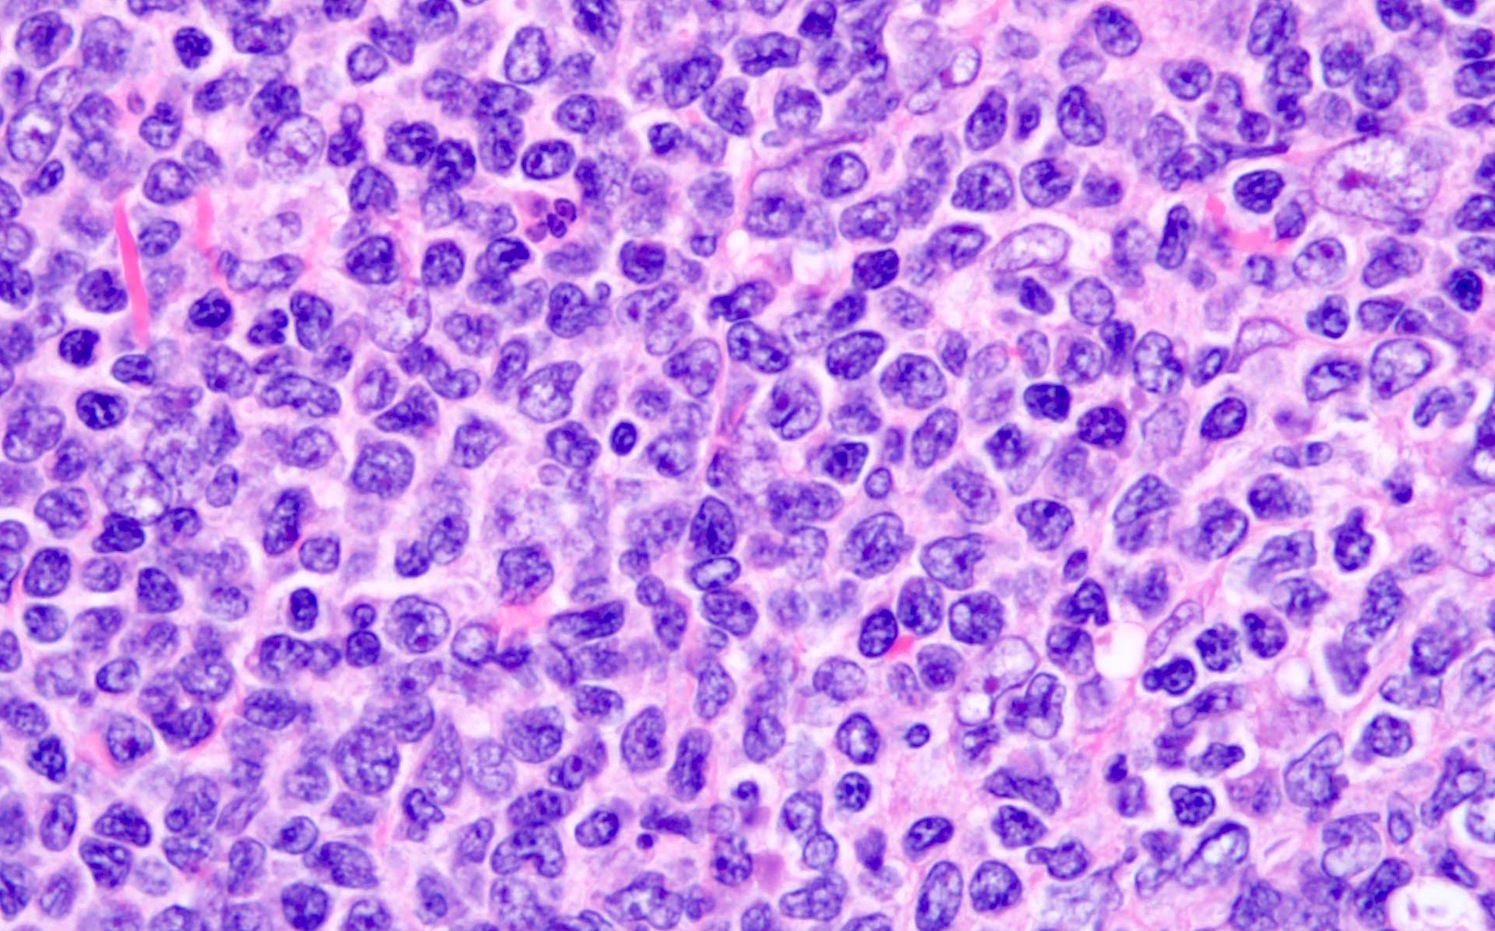

- Pleomorphic variant

- Variable size / heterogenous cell population including large cells

- Prominent nucleoli +/-

- High mitotic rate often seen

- At least 10 mitoses per 10 high power fields and often higher rates

- Resembles, in part, diffuse large B cell lymphoma

- Peripheral blood lymphocytes are intermediate sized with prominent nucleoli

- Resemble prolymphocytes to variable degree

- Multinucleation or cerebriform nuclei often seen

Microscopic (histologic) images